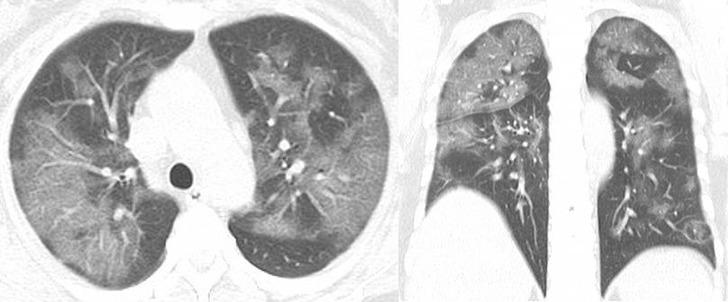

Covid-19'dan kaynaklı zatürre hastası 54 yaşındaki bir kadının transversal ve koronal bilgisayarlı tomografi (BT) görüntülerinde pulmoner lezyonların üst lobda daha yaygın olduğu görülüyor.

Vuhan kentinden döndükten sonra bir hafta boyunca ateşi 38.5 dereceden düşmeyen kadına, nefes darlığı, öksürük ve halsizlik semptomlarıyla hastane yattıktan sonra Covid-19 testi yapıldı. Test sonuçları pozitif çıkan hastaya zatürre teşhisi kondu. Uygulanan tedaviyle söz konusu hastanın semptomlarının hafiflediği rapor edildi.